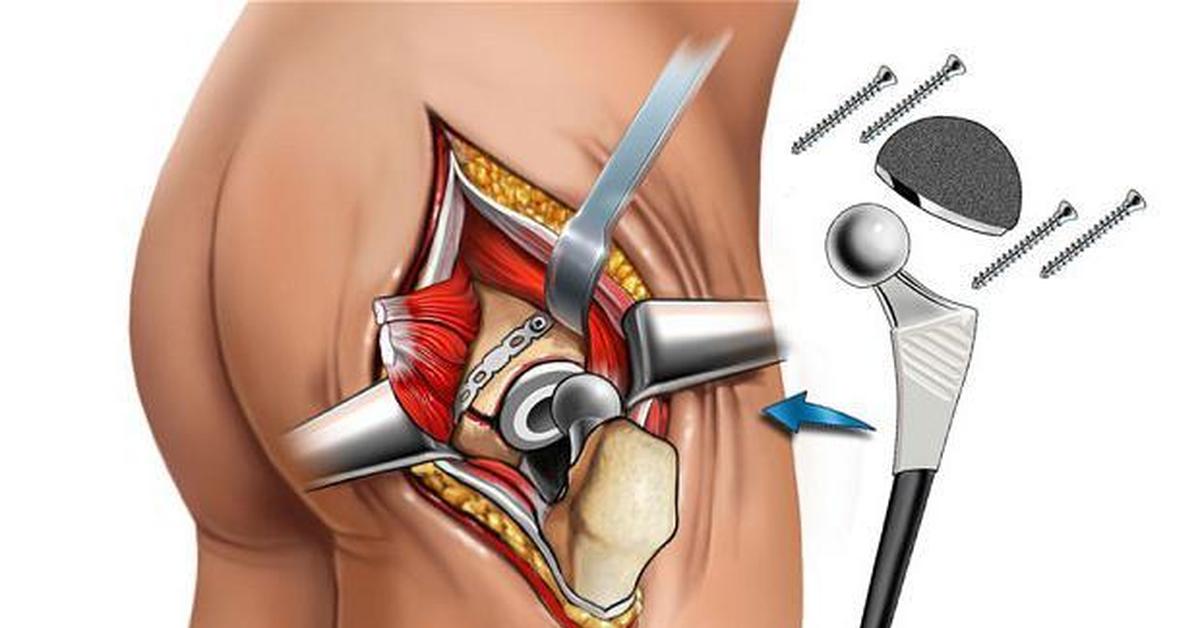

Эндопротезирование тазобедренного сустава: фото и схемы